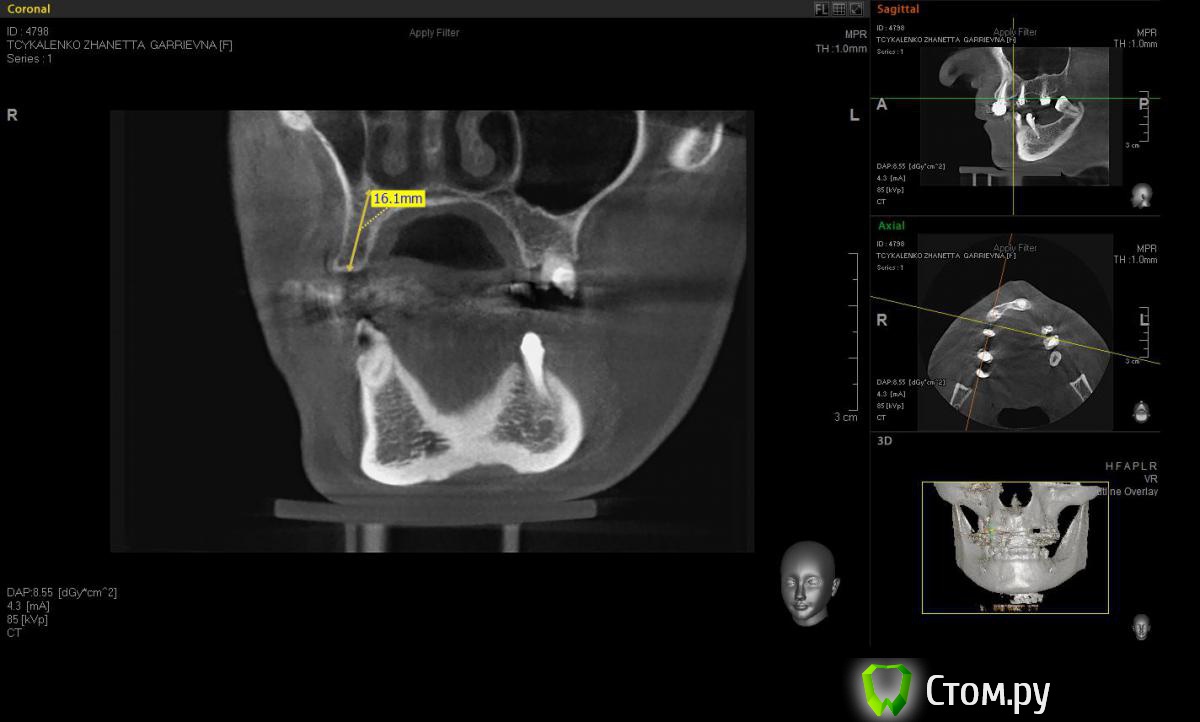

Евгений Ходыкин Опубликовано 20 мая, 2014 Автор Поделиться Опубликовано 20 мая, 2014 Замерил... Ссылка на комментарий

АнтонТЛТ Опубликовано 20 мая, 2014 Поделиться Опубликовано 20 мая, 2014 А теперь замерьте угол в районе 15 зуба через фиссуру Ссылка на комментарий

Евгений Ходыкин Опубликовано 20 мая, 2014 Автор Поделиться Опубликовано 20 мая, 2014 Ну как-то так. Сути не уловил) Свой зуб стоит совсем иначе, да и ширина гребня иная совсем... Ссылка на комментарий

АнтонТЛТ Опубликовано 20 мая, 2014 Поделиться Опубликовано 20 мая, 2014 Суть в том, что изначально не правильно угол замерили 1 Ссылка на комментарий

Евгений Ходыкин Опубликовано 20 мая, 2014 Автор Поделиться Опубликовано 20 мая, 2014 Суть в том, что изначально не правильно угол замерилиДак изначально я замерил строго по гребню, в условиях наибольшей ширины гребня, там угол под 30 и выходил. При ангуляции как у 1.5 у меня и получается дефицит кости, что примерно изобразил на схеме постановки имплантата. Поправьте, если не прав... Ссылка на комментарий